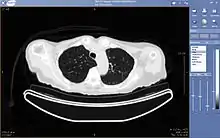

La téléradiologie consiste en la consultation et l'interprétation d'images radiologiques ou échographiques à distance.

C'est l'exploitation de la transmission d’images pour l'obtention à distance d'un diagnostic primaire et définitif, en l'absence, auprès du patient d'un radiologue pour interpréter immédiatement ces images. Généralement les équipes de radiologues assurant ce service peuvent réaliser des vacations ou même de simples plages horaires réduites pour toutes modalités d'imagerie afin de permettre d'assurer un service continu pour les patients. Les solutions présentées sont la plupart du temps sécurisées et respectent les recommandations du CNOM et de la DHOS. Elles sont adaptées aux besoins hospitaliers mais aussi aux cliniques ou cabinets libéraux.

Cette activité consiste en l'envoi, par réseau, des données produites par une structure médicalisée et disposant d'un radiologue vers une seconde structure ayant un niveau d'expertise supérieur. Cela permet d'analyser les dossiers les plus complexes, et d'avoir l'avis d'experts spécialisés dans leur domaine de compétences.